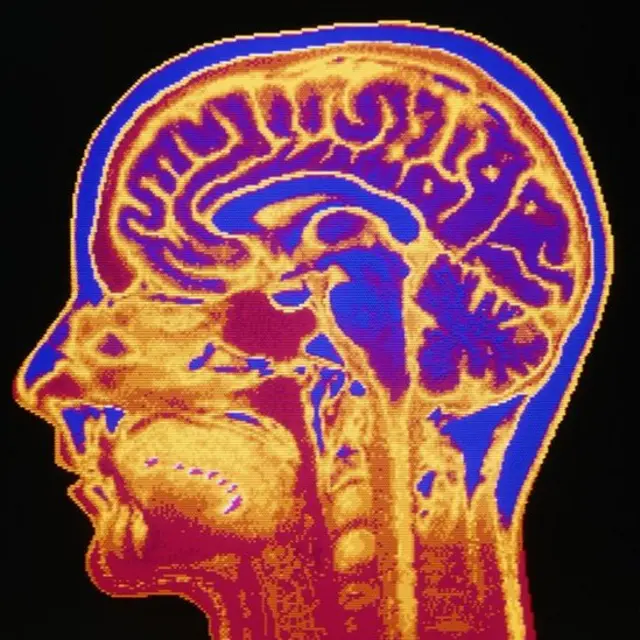

Sus escáneres mentales eran normales, lo que sugería que la causa era más psicológica que neurológica.

El doctor Akira O'Connor, un psicólogo de la Universidad de St Andrews, en Escocia, cree que podría deberse a un momentáneo "arranque en falso" de neuronas, lo que generaría conexiones engañosas en el cerebro.

"Una idea es que el 'déjà vu' es una especie de 'contracción' del cerebro. De la misma manera en la que tenemos espasmos musculares u oculares, podría ocurrir que la parte de nuestro cerebro que envía señales que tienen que ver con la familiaridad y la memoria esté operando mal", dice.

Y asegura que esta explicación encaja con los datos que señalan una mayor incidencia del fenómeno en personas con epilepsia o demencia.

"Esto último implica lidiar con varios problemas, como el vértigo. Pero uno de los efectos secundarios más comunes es el 'déjà vu'. Se ha sugerido que es porque el canal auditivo está cerca del lóbulo temporal", dice.

Y es que esa parte del cerebro desempeña un papel importante en tareas visuales complejas, como el reconocimiento de caras.